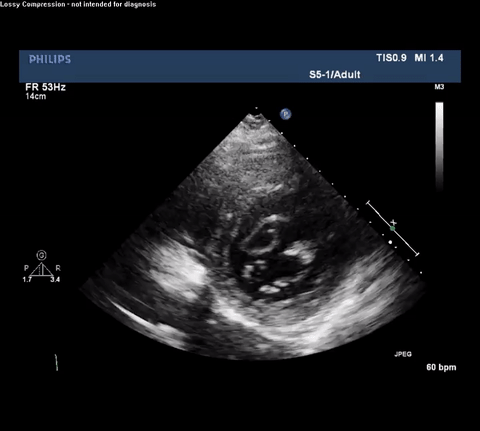

TTE Parasternal Short Axis View

Despite these shortcomings, cardiac POCUS can be performed quickly and does

not require either transport or IV contrast. This case illustrates how

intensivists performing routine cardiac POCUS exams need to be able to

identify both direct and indirect signs consistent with TA-AAD or else an

opportunity to provide expedited care may be missed. For example, it is

important to recognize the presence of an intimal flap which must be

differentiated from reverberation or mirror artifact originating from nearby

structures. Color Doppler can aid in identifying both true and false lumens

along with aortic regurgitation. Finally, depending on the clinical setting

other findings may be associated with TA-AAD and should raise concern for this

diagnosis including: bicuspid aortic valve, dilated aortic root, aortic

regurgitation and pericardial effusion.